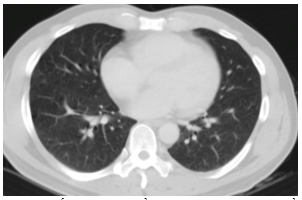

Chụp cắt lớp vi tính lồng ngực: Hình ảnh các nốt kính mờ rãnh liên thùy và màng phổi phải.Đám dải xẹp phổi thùy giữa phổi phải

Hình 7: Hình ảnh chụp cắt lớp vi tính lồng ngực sau điều trị, tổn thương u giảm kích thước sau 6 tháng điều trị (mũi tên vàng)